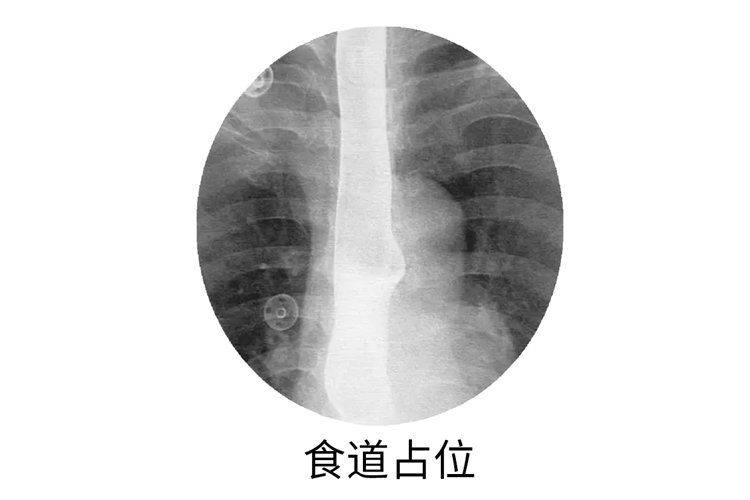

?2.占位

是指超声诊断中对病灶的称呼 , 小的称为结节 , 大的就叫占位 。

占位性病变包括很多疾病 , 如良性肿瘤 , 恶性肿瘤 , 寄生虫病、炎性假瘤等等 , 该检查结果是一大类病变的统称 , 只是形态学描述 , 不涉及疾病的病因、性质 , 具体还要问相应医生 。